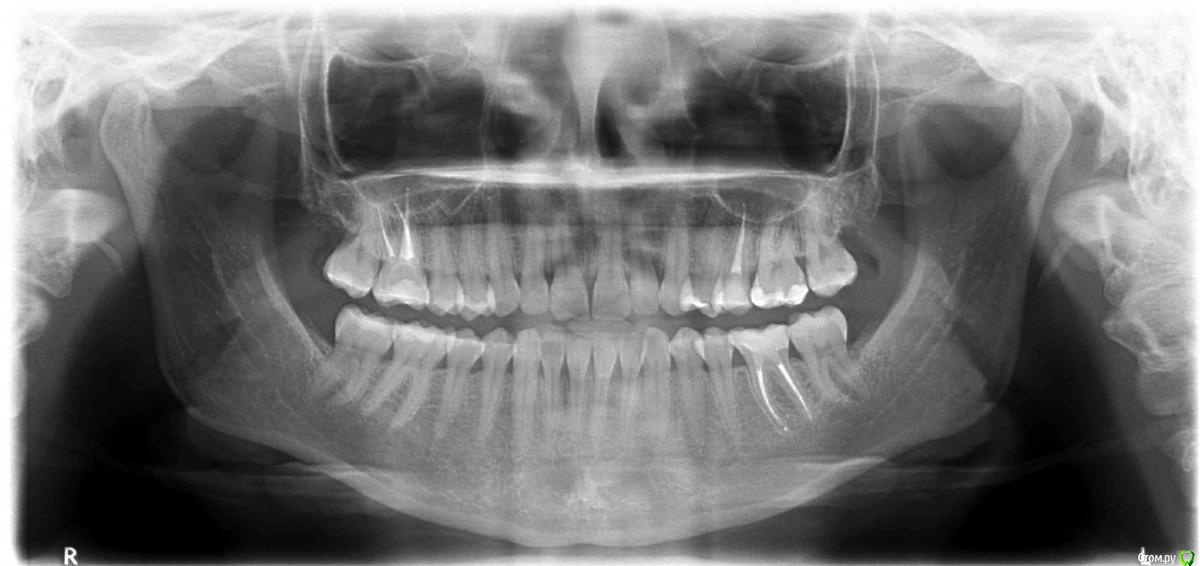

felicidade Опубликовано 15 февраля, 2015 Автор Поделиться Опубликовано 15 февраля, 2015 Добрый день, уважаемые доктора 36 зуб поживает нормально, ТТТ. У меня большая просьба: не могли бы вы сказать, если ли хоть минимальные признаки уменьшения кисты под ним после перепломбировки каналов (июль 2014)?Вот ОПТГ до перелечивания (апрель 2014). Тут уже октябрьская ОПТГ, а вот тут - свежайшая февральская (2015).Надеюсь, что если киста и не уменьшилась, то хоть кариесов новых нет А также, пользуясь случаем, ещё раз очень благодарю всех, кто поучаствовал в судьбе спасения зуба этим летом! Ссылка на комментарий

felicidade Опубликовано 6 ноября, 2015 Автор Поделиться Опубликовано 6 ноября, 2015 Здравствуйте! Это снова я Сегодня сделала контрольную ОПТГ (спустя 1г 3 мес после перепломбировки №36 и спустя 9 мес с момента последней ОПТГ). Эту не самую качественную ОПТГ я сделала вообще у ортодонта, т.к. у остальных стоматологов в нашем регионе запись новых пациентов на панорамный снимок+профилактический осмотр идёт самое раннее на январь 2016, а самое позднее - на май В общем, сейчас снова возьмусь за обзвон местных докторов, авось кто и примет меня пораньше с уже готовым снимком. А у меня, пока ищу стоматолога, снова нескромная просьба бегло оценить состояние челюсти: в апреле я наконец-то удалила верхние ретинированные зубы мудрости, ну, и, как всегда, у меня паническая боязнь вторичного кариеса под пломбами.. Всем ещё раз спасибо и хороших выходных! Ссылка на комментарий

felicidade Опубликовано 7 февраля, 2017 Автор Поделиться Опубликовано 7 февраля, 2017 (изменено) Добрый день, уважаемые господа стоматологи Вчера была на профилактической чистке зубов, заодно попросила сделать ОПТГ . Стоматолог сказал, что всё нормально - если не сложно, подтвердите или опровергните его мнение, пожалуйста Спасибо заранее! Изменено 7 февраля, 2017 пользователем felicidade Ссылка на комментарий